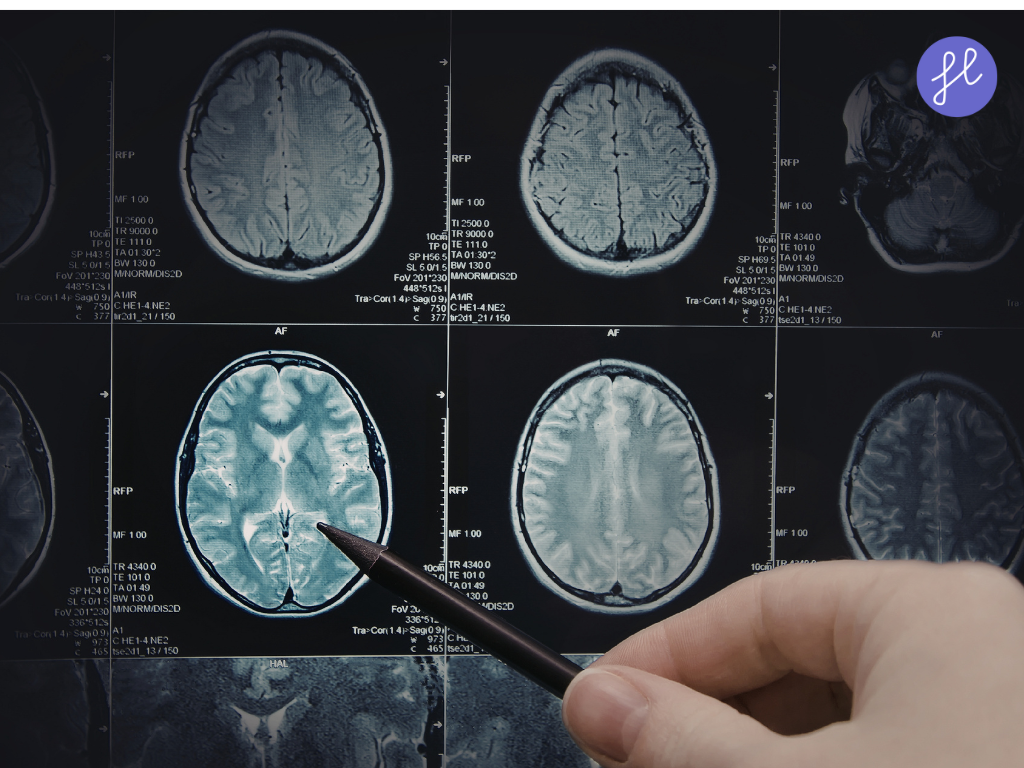

- Computer Vision: Allows AI to interpret visual data like X-rays, MRIs, and CT scans.

1. Medical Imaging Analysis

AI excels in interpreting imaging data, often outperforming human radiologists in accuracy and speed. AI algorithms, particularly Convolutional Neural Networks (CNNs), are now the gold standard for “first-pass” screenings.

AI helps diagnose Alzheimer’s, Parkinson’s, and multiple sclerosis by analyzing brain imaging and cognitive data.